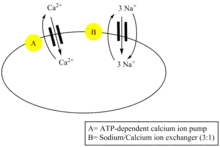

β-Antiarin is administered to the body through injection. Once inside the body, the chemical will affect muscular and cardiac tissues.[5] A heart attack occurs because beta-antiarin affects Na+K+-ATPase cardiac-muscle membrane activity.[3]

However, the very effect that allows β-antiarin to be a poison also gives it medicinal properties. It limits the sodium ion (Na+) concentration by blocking the Na+ pump, which then promotes calcium ions (Ca2+) to increase in concentration in the extracellular cardiac muscle domain, therein permitting the heart to contract.[7] The mechanism through which sodium and calcium ions are exchanged, known as the sodium-calcium exchanger, allows for the exchange of ions to occur at a rate of 3:1 respectively. The cardiac cell exhibits a positive potential during ventricular systole, becomes depolarized, and permits calcium ions to rush in by the sodium-calcium exchanger. From here, the contraction occurs when the calcium ions leave and the cell re-polarizes.[8] If the dosage of cardiac glycoside (i.e. beta-antiarin) doubles, then the substance becomes a poison.[7]